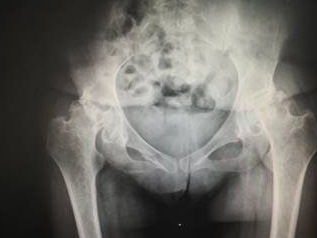

“最近走路总感觉一条腿使不上劲,不知不觉就瘸了”,不少人出现这种…… 【详情】

“髋关节突然疼了一下,过会儿又好了”,很多人遇到这种情况会不以…… 【详情】